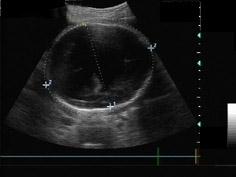

36周胎儿头部超声检查如图,根据声像图初步诊断应该为 ( )A、孔洞脑B、小脑蚓部缺损C、脑积水D、先天性蛛网膜囊肿E、无脑畸形

问题 36周胎儿头部超声检查如图,根据声像图初步诊断应该为 ( )

选项 A、孔洞脑 B、小脑蚓部缺损 C、脑积水 D、先天性蛛网膜囊肿 E、无脑畸形

答案 C